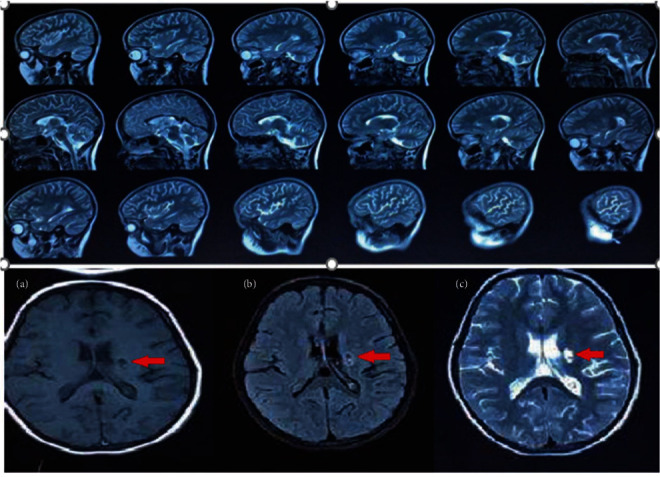

Background: Adenosine deaminase deficiency 2 (DADA2) is an autoinflammatory disorder, caused by the CECR1 gene mutation. The major clinical manifestations include recurrent vasculitis, neurological disorders such as stroke, hematologic abnormalities, and immunodeficiency. As reported in previous studies, DADA2 may be manifested by ischemic or hemorrhagic strokes. This disorder also includes various hematological manifestations (pure red cell aplasia, pancytopenia, hemolytic anemia, and pancytopenia with bone marrow involvement). Case Presentation. In this case report, we present the clinical and immunological findings of two unrelated patients with DADA2. The first patient was a 7-year-old female who experienced recurrent neurological symptoms such as vertigo, tinnitus, hearing loss, and right-sided hemiparesis. Her brain magnetic resonance imaging (MRI) revealed a left-sided stroke, and she responded well to antitumor necrosis factor alpha agents and plasmapheresis. The second patient was a 6-year-old female who had recurrent fever and bicytopenia, aphthous lesions, cervical lymphadenopathy, and elevated liver enzymes. We also discussed the strategies used to manage the clinical manifestations in these two DADA2 patients.